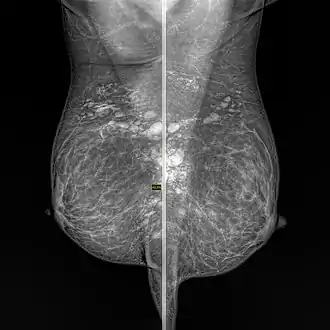

| Snowball like hyperechogenic axillary lymph nodes in a woman with silicone implants removed due to complications | |